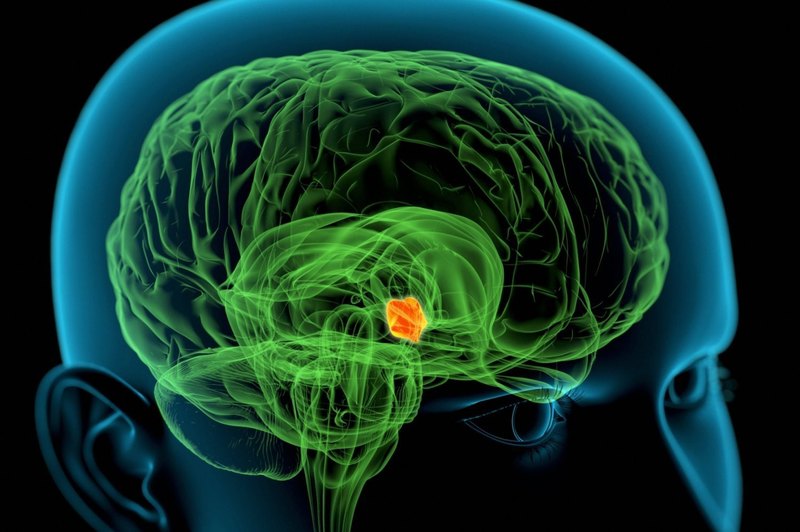

Элевационная (онтогенетическая) теория

В начале 1950-х отечественный геронтолог В.М. Дильман выдвинул и обосновал идею о существовании единого регуляторного механизма, определяющего закономерности возрастных изменений различных гомеостатических (поддерживающих постоянство внутренней среды) систем организма. По гипотезе Дильмана, основным звеном механизмов как развития (лат. elevatio — подъем, в переносном смысле — развитие), так и последующего старения организма является гипоталамус — «дирижер» эндокринной системы. Главная причина старения — это возрастное снижение чувствительности гипоталамуса к регуляторным сигналам, поступающим от нервной системы и желез внутренней секреции.

По Дильману, старение и связанные с ним болезни — это побочный продукт реализации генетической программы онтогенеза — развития организма. Онтогенетическая модель возрастной патологии открыла новые подходы к профилактике старения и болезней, связанных с возрастом и служащих основными причинами смерти: заболеваний сердца, злокачественных новообразований, инсультов, метаболической иммунодепрессии, атеросклероза, сахарного диабета пожилых и ожирения, психической депрессии, аутоиммунных и некоторых других заболеваний. Из онтогенетической модели следует, что если стабилизировать состояние гомеостаза на уровне, достигаемом к окончанию развития организма, то можно затормозить развитие болезней и естественных старческих изменений и увеличить видовые пределы жизни человека. Знать бы только, как…